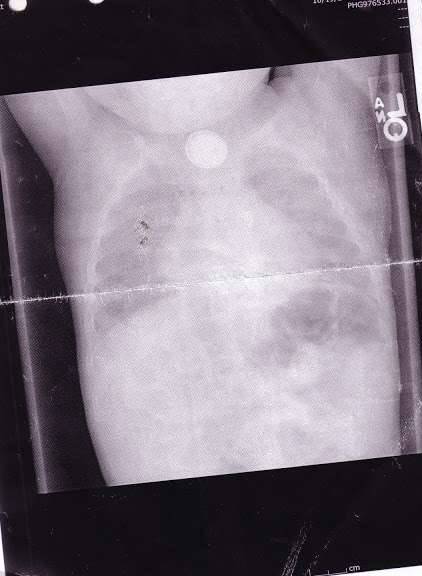

▼卡拉和麦可半信半疑地回家了,几天后艾密特的状况却变本加厉,开始咳血!心慌的他们立刻带艾密特到了急诊室,急诊室的医生对艾密特照了X光,然后就发现这可怕的一幕…

▼他们清楚地看到艾密特的小小身躯里卡了钮扣电池,而且电池里释放的硷性物质,已经大大破坏了他的食道和消化道,只要再晚点发现,就会造成这个1岁男童的死亡。